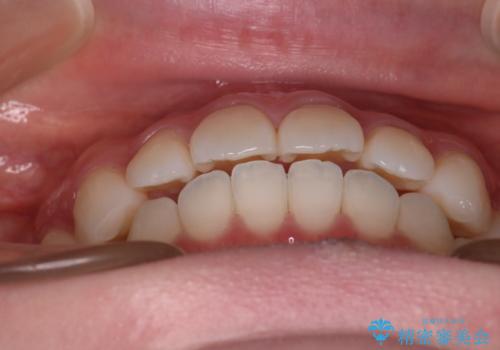

- 前歯の捻転とかみ合わせを主訴に来院されました。今回は抜歯をせずにIPRを実施し、並べる計画を立てました。

ワイヤー矯正を行いながら、顎間ゴムを患者さまにご協力していただき、短い期間で終了できました。